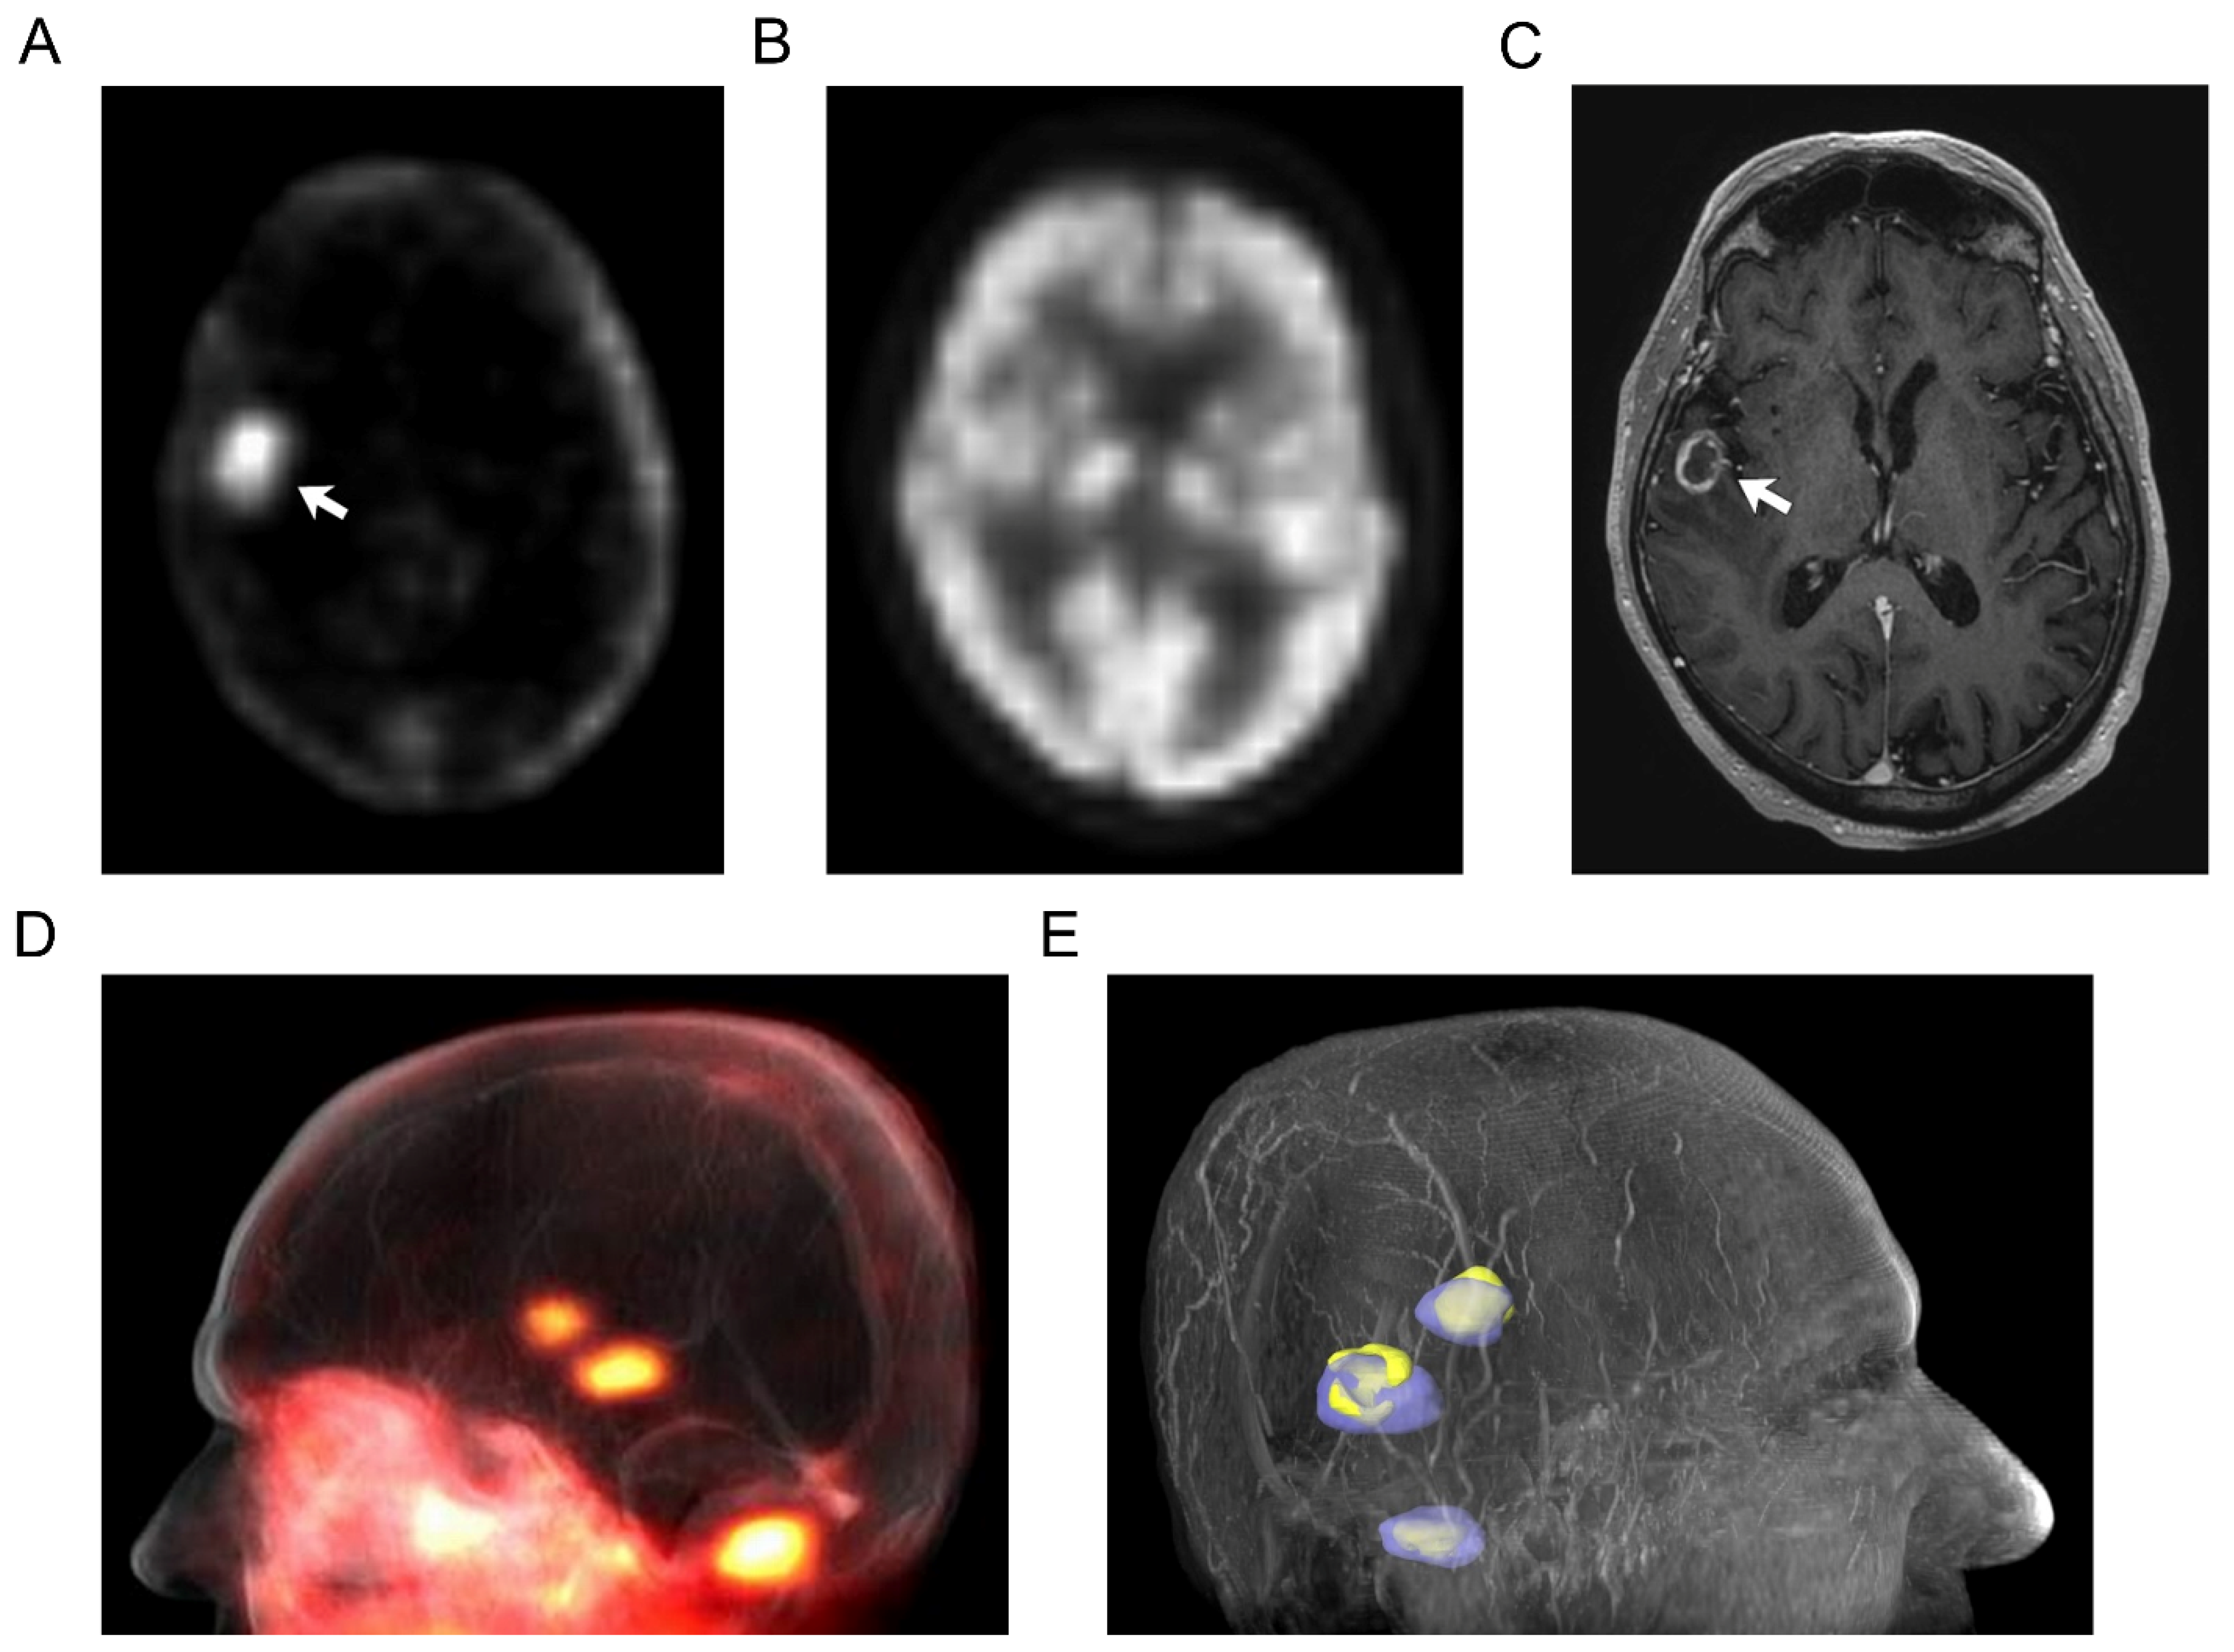

In contrast to standard clinical nuclear imaging, brain lesions were well depicted with [124I]I-NM404 PET imaging due to the high tumor-to-background activity (Figure 1) with [18F]FDG PET imaging, brain metastases are generally not detectable, largely due to the high level of [18F]FDG avidity for normal brain tissue (Figure 1B). However, at subsequent follow-up MR imaging (Figure 1C), the nonspecific enhancing lesion has continued to enlarge, associated with progressive perilesional edema, more concerning for metastatic disease, and prompting close clinical follow up. In this patient with primary bronchogenic carcinoma, the detection of clinically unsuspected, [18F]FDG PET occult, brain metastases by [124I]I-NM404 PET altered the treatment plan.

Figure 1. Unsuspected brain metastases in 70-year-old man with primary bronchogenic carcinoma. Transverse PET image (A) obtained 6 days after injection of 185 MBq [124I]I-NM404 shows a right hemispheric focus of activity (arrow) that was not detectable on [18F]FDG PET (B) but confirmed on subsequent contrast-enhanced MR ((C), arrow). Fused volume-rendered [124I]I-NM404 PET-MR image (D) shows a total of three unsuspected brain metastases (2 cerebral and 1 cerebellar) that were identified on [124I]I-NM404 PET and confirmed on MR, which altered the treatment strategy for this patient. Additional fused volume-rendered [124I]I-NM404 PET-MR image (E) with segmentation of the brain metastases shows the regions of [124I]I-NM404 uptake (purple), which exceed the regions of abnormal MR contrast enhancement (yellow). The clinical significance of this uptake-enhancement discordance within the tumor is uncertain.